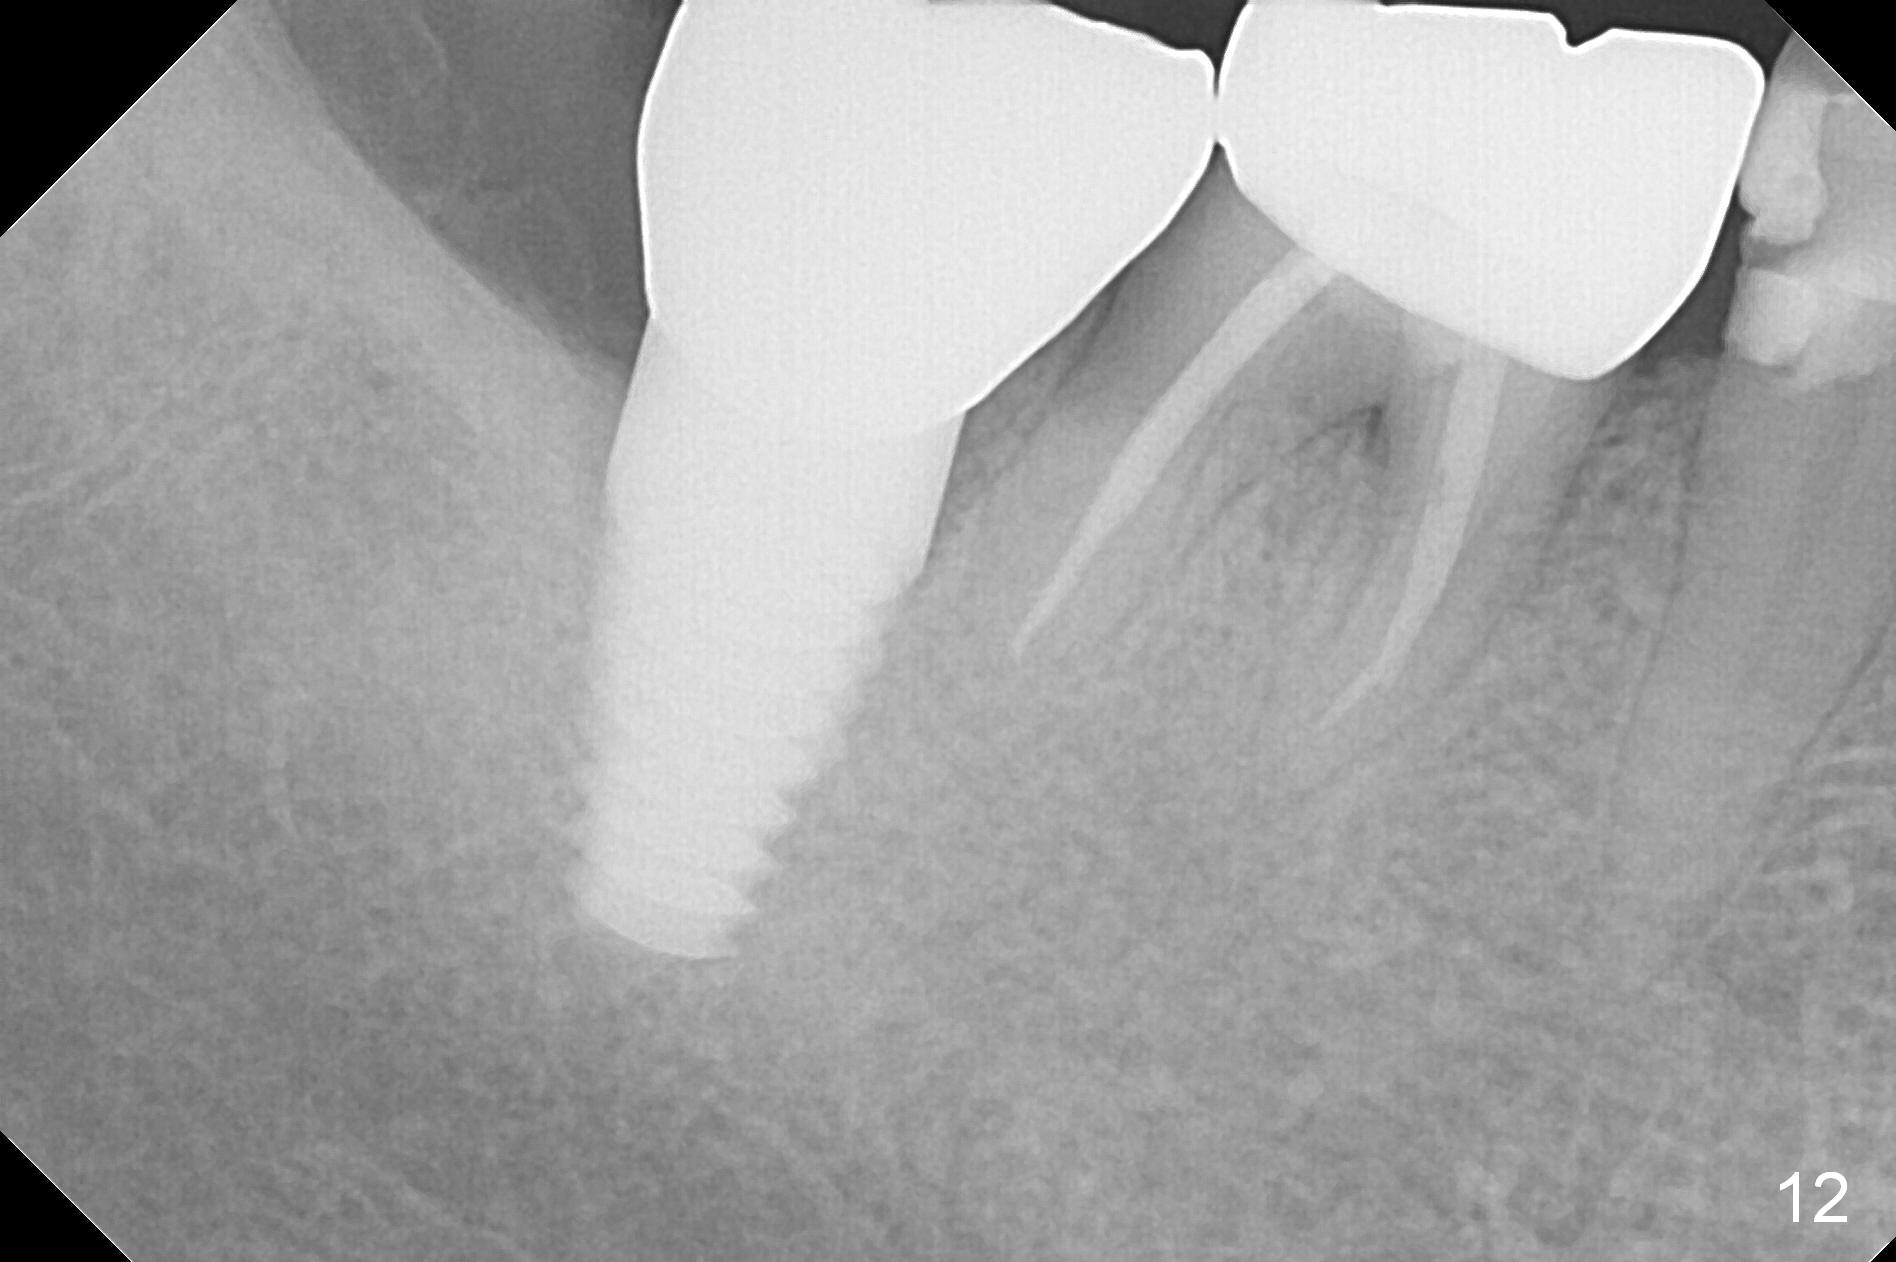

Mrs. Hwang in her sixties has had periodontal disease in her lower right 2nd molar (Fig.1 *). Three years later, both the 2nd and 3rd molars are extracted (Fig.2; pink: the upper border of the inferior alveolar canal). Four months after extraction, the patient returns for implant placement at the site of #31 (Fig.3, 4). The socket of the 2nd molar is outlined in yellow in Fig.3.

An intraop PA is taken with 4x14mm tapered drill in place (Fig.5 D). It appears that the osteotomy is deviated to the mesial portion of the healed socket (yellow outline). While the top of drill is at the gingival level (arrowheads), the tip of drill is 3.34 mm from the inferior alveolar nerve.

A postop PA is taken immediately after 6x14 mm tapered implant is placed (Fig.6 I). The top of the implant remains at the gingival level (white arrowheads). The implant is later further torqued down about 0.5 mm (red arrow).

Three years 8 months post cementation, the crown dislodged. A 5x3 mm 0 ° unipost is resin bonded. Retrospectively the angled abutment appears not necessary (Fig.13 (occlusal view), 14 (posterior view)). Fig.12 is taken immediately post cementation of redo crown. There is no bone loss.